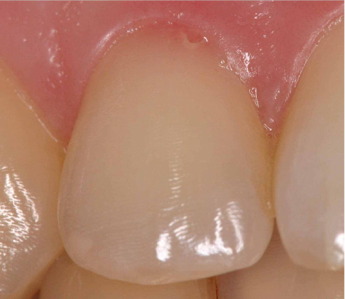

Lesión Traumática Pulpar

Una lesión traumática pulpar es un daño a la pulpa dental debido a un trauma, como un golpe en el diente.

Los pacientes pueden experimentar dolor, sensibilidad y decoloración del diente.

El tratamiento incluye evaluar la vitalidad de la pulpa y, si es necesario, realizar un tratamiento de conducto. Es importante tratar la lesión para evitar complicaciones a largo plazo.